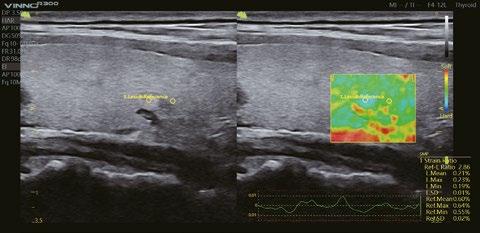

Intelligente Erfassung und Stadieneinteilung von Schilddrüsenerkrankungen

Schilddrüsenknoten werden in Echtzeit oder auf gespeicherten Bildern erkannt, zusammen mit dem T-RADS-Kategorisierungs- und Berichtstool, wodurch die klinische Routine der Schilddrüsenultraschalluntersuchung genauer und aussagekräftiger wird.

Messung der relativen Steifigkeit zwischen der Läsion und dem Referenzbereich, um Patienten mit Lebererkrankungen zu überwachen und die Ansatzpunkte für Biopsien zu lokalisieren und frühe Anzeichen einiger Krebsarten zu erkennen.